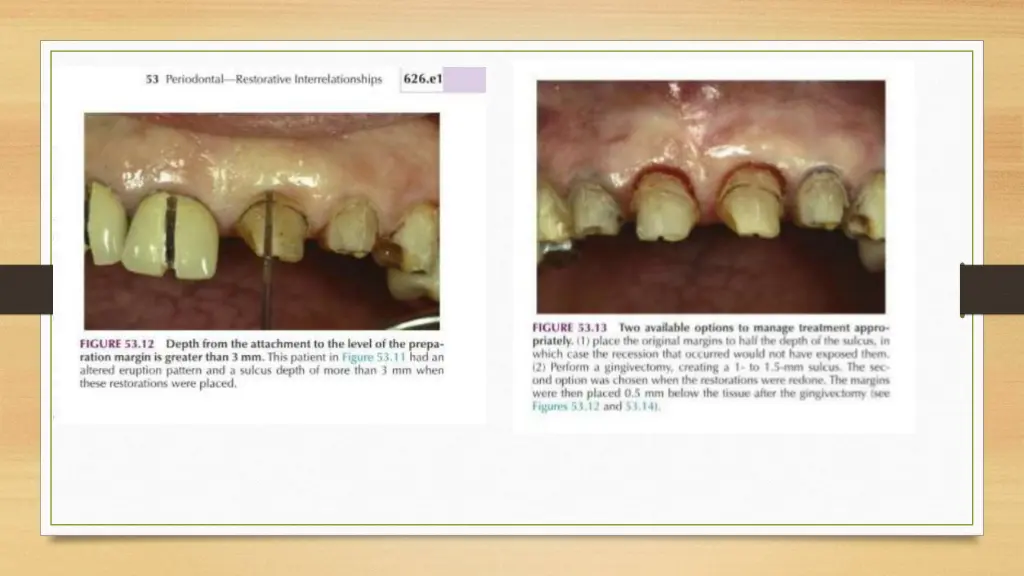

MARGIN PLACEMENT GUIDELINES i. If the sulcus probes 1.5mm or less,Place the margin 0.5mm below the gingival crest. ii. If sulcus probes more than 1.5mm- Place the margin 1\2 depth of the sulcus below the crest. iii. If sulcus probes more than 2.0mm, Esp. On facial aspect- Gingivectomy should be done & create a 1.5mm sulcus Apply Rule No. 1

Anterior Aesthetic Surgery More Imp. In Anterior Region Gingivectomy, Apically displaced flaps with osseous recontouring & Use of Orthodontics in positioning the gingiva apically or coronally by Extruding or Intruding the teeth. Computer Imaging for Visual preview A Stone cast of patient s own teeth may be used Composite or Acrylic veneer is constructed on the cast extending gingivally in a correct position.